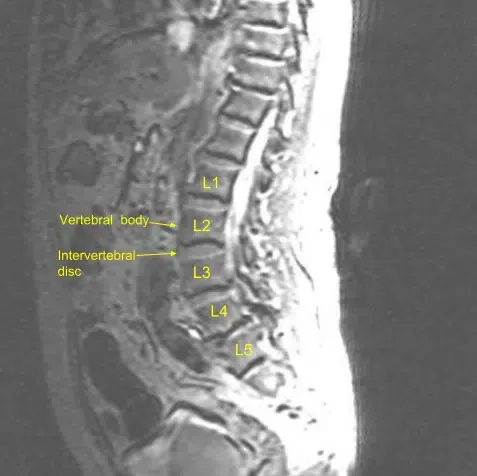

Vista sagital de la resonancia preoperatoria de la columna lumbar

El ligamento flavio estaba severamente hipertrofiado, correlacionado con la imagen preoperatoria. Una vez verificada que estaba terminada, la cama se cepilló al aire y el separador tubular se inclinó hacia el lado izquierdo contralateralmente sobre la parte superior. Se realizó laminotomía en el lado izquierdo en L4-L5. La duramadre fue cuidadosamente protegida con algodón mientras se resecaba el ligamento flavo hipertrofiado contralateral.